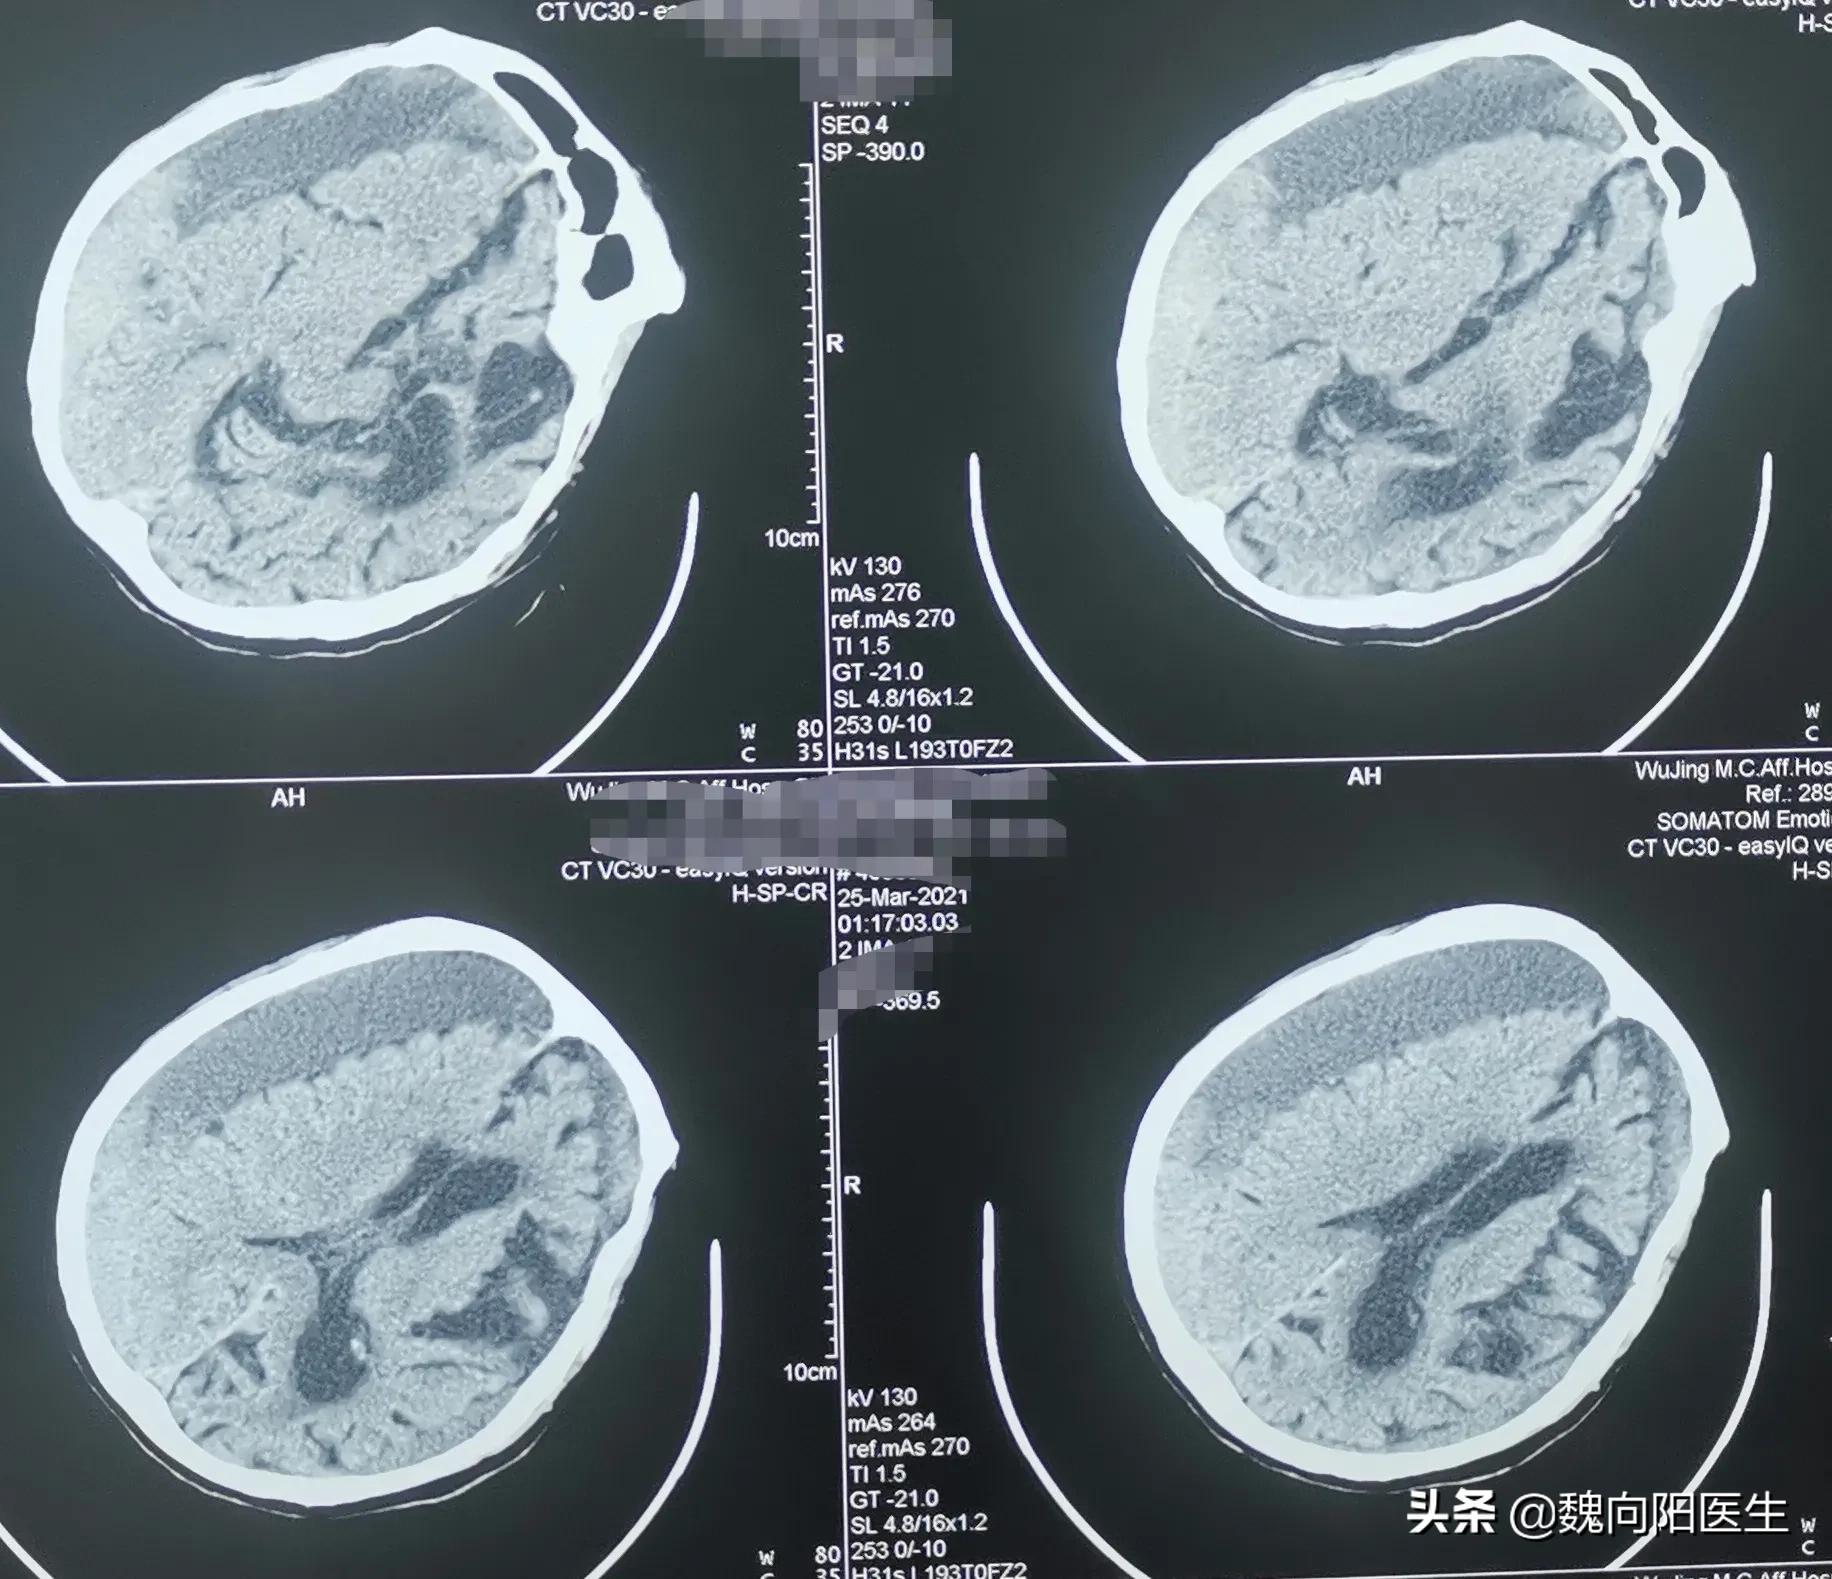

在大冶卧床半个月之后,出现了昏迷现象,家属终于按耐不住将老人送到了医院,查一个头CT提示:“慢性硬膜下血肿”。

慢性硬膜下血肿 (chronic subdural hematoma,CSDH)是血液集聚在蛛网膜与硬脑膜之间形成的慢性占位性病变,常在头部外伤3周以后形成。